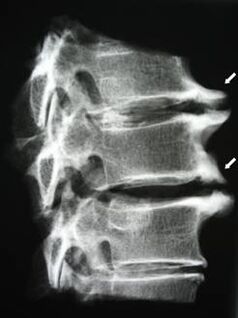

Pradinėse stadijose osteochondrozė nustatoma naudojant MRT. Vėliau patologiją galima diagnozuoti naudojant rentgenografiją. Kaklo stuburo rentgenogramose pastebimas atstumo tarp slankstelių sumažėjimas, fasetinių sąnarių patologiniai pokyčiai, osteofitozė.

| Gimdos kaklelio osteochondrozė | Patologinių pokyčių atsiradimas viename ar keliuose stuburo judesio segmentuose. Sutrinka stuburo paslankumas, išsivysto miofascialiniai skausmo sindromai ir stuburo šaknų užspaudimas | Skausmas, parestezija ir motorikos sutrikimai gimdos kaklelio srityje, kurie plinta į pakaušį ir viršutines galūnes. Būdingų stuburo pakitimų nustatymas MRT ir rentgenogramose (osteofitai, sumažėjęs atstumas tarp slankstelių, tarpslankstelinių sąnarių pažeidimo požymiai) |